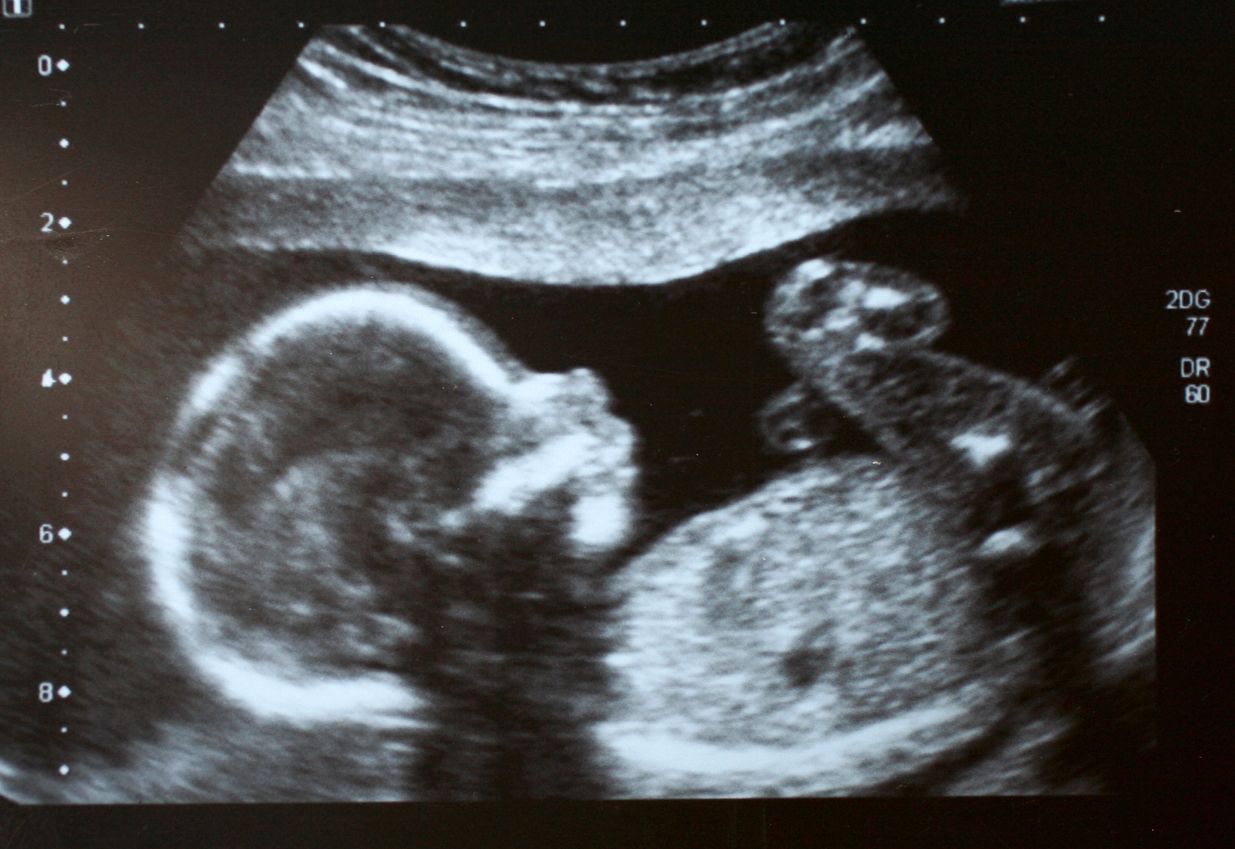

Studien haben ergeben, dass das Baby nicht nur den Herzschlag der Mutter hören kann, sondern auch das Gurgeln des Verdauungssystems, ihre Stimme und den Blutfluss.